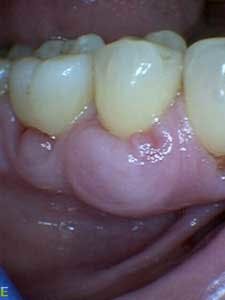

Dental examination revealed gingival swelling and bleeding on probing. Periodontal probing showed moderate-to-deep pocket depths in all posterior teeth (figures 1–3). Generalized bone loss was observed on radiographs (figures 4–6). Tooth vitality and percussion tests were negative. Teeth 2, 3, 31, 14, and 15 had Class III mobility. The patient was diagnosed with Type IV chronic adult periodontitis. Treatment options were discussed, and, after explanation, the patient agreed to the LANAP procedure.

Patient presentation before LANAP treatment (figures 1–6)